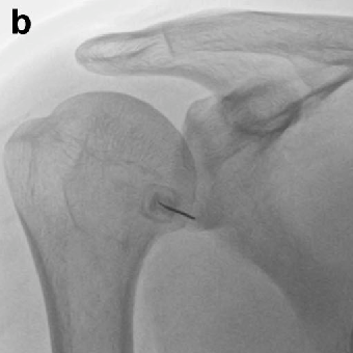

오십견의 치료

관절 가동 범위를 확대하기 위해 관절낭 팽창술과 함께 인대강화주사를 할 수 있으며 이 후 재활기간 동안 어깨관절도수를 시행하게 됩니다. 심각한 오십견의 경우 어깨부위를 마취하고 수동 조작을 통해 어깨 관절 가동범위를 정상화 할 수 있습니다.